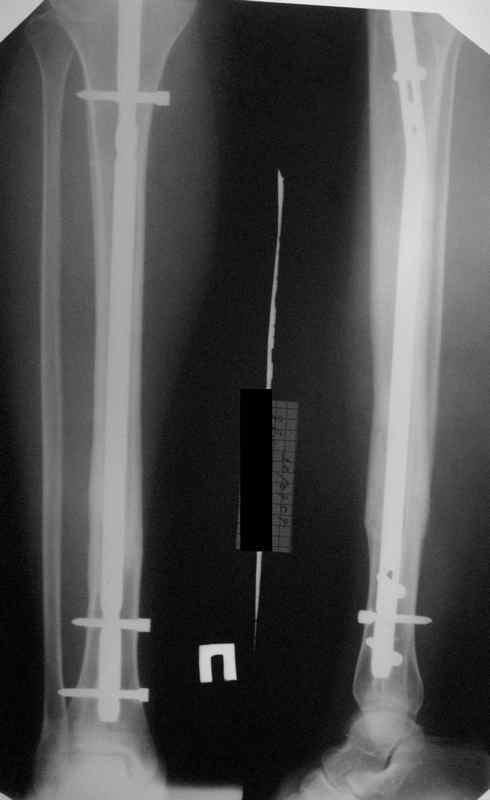

Посмотрев на клинический случай с винтообразным переломом ББ и МБ костей, возник вопрос о целесообразности динамизации фиксатора при подобном типе перлома.

Винтообразный перелом создает обширную зону межфрагментарного контакта, что является благоприятным условием для консолидации, если в ожидаемые 8-10 недель мозолеообразования не наблюдается, то динамизация приводит к *соскальзыванию* проксимального фрагмента- вторичному смещению, величина которого и определяется размером овального окна гвоздя.

Логичным, на мой взгляд, в подобной ситуации является не динамизация гвоздя, а смена гвоздя на больший размер с рассверливанием.

Динамизация скорее показана при поперечных/ short oblique типах, когда зона межфрагментарного контакта ограничена, нет риска вторичного смещения отломков.